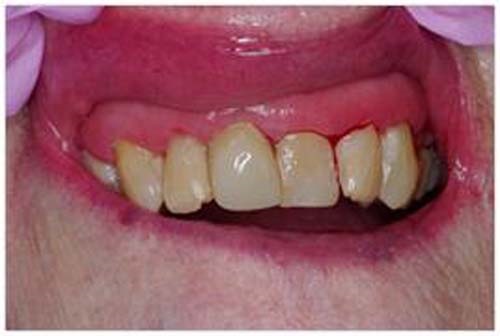

At 94, the patient still had a full set of natural teeth, thanks to a lifelong commitment to oral care, but she now suffered from compromised hygiene, xerostomia and a tendency to retain some food in her mouth. A radiograph revealed extensive caries, but the bone was excellent. Fortunately, she is cared for by a loving daughter who wanted her mother’s tooth restored for her comfort and appearance.

After removal of the caries (Fig. 3, p. 27) I fitted a generic strip crown and marked the junction to her facial enamel on the crown form (Fig. 4, p. 27). This allowed me to know exactly where to place the darker conventional composite as a facial veneer (Fig. 5). This veneer would not interfere with the benefits of the flowable bioactive composite for both the placement and the sustainability of the restoration.

Fig. 2: Radiograph of incisor.